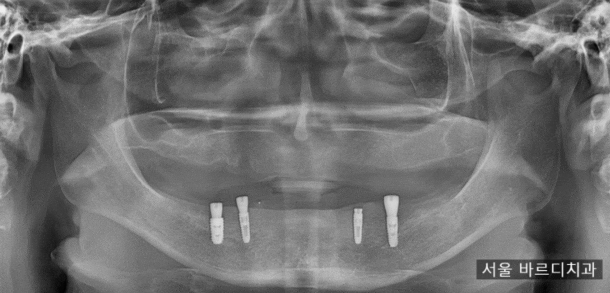

치아가 거의 없는 상태로 하남미사치과 내원해 주셨습니다.

위에 치아는 뿌리만 남고

아래 치아도 1개만 남아있네요.